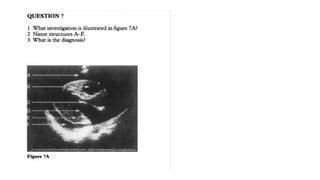

Dr Abdul, Dr Wakaba

TTE